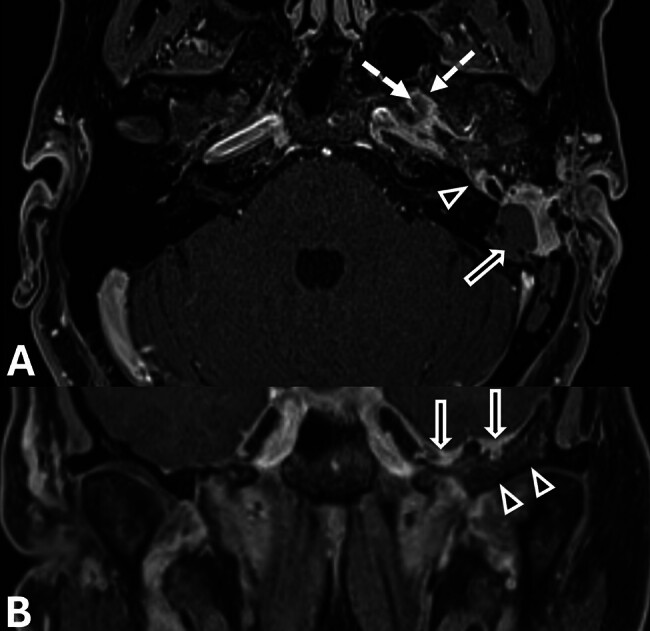

Temporal bone en plaque meningiomas can present management challenges, particularly when accompanied by severe pain. We report the case of a 42-year-old woman who was initially diagnosed with chronic otitis media but was later found to have a painful left temporal bone en plaque meningioma. Despite conservative therapy, her pain progressed, prompting the decision to undergo surgical resection, which resulted in considerable pain relief. This report illustrates the influence of pain on surgical decision-making for temporal bone en plaque meningiomas and reviews the literature on their variable presentations and management strategies.